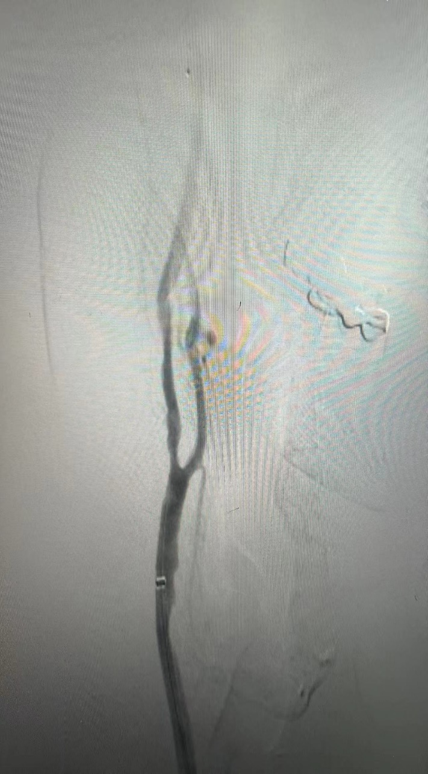

CASE 2:69岁男性,左侧颈动脉支架术后再狭窄,IVL治疗后管腔获得良好,支架置入后残余狭窄低。

左侧颈动脉支架

术后再狭窄

IVL后管腔

获得良好

支架后

残余狭窄低